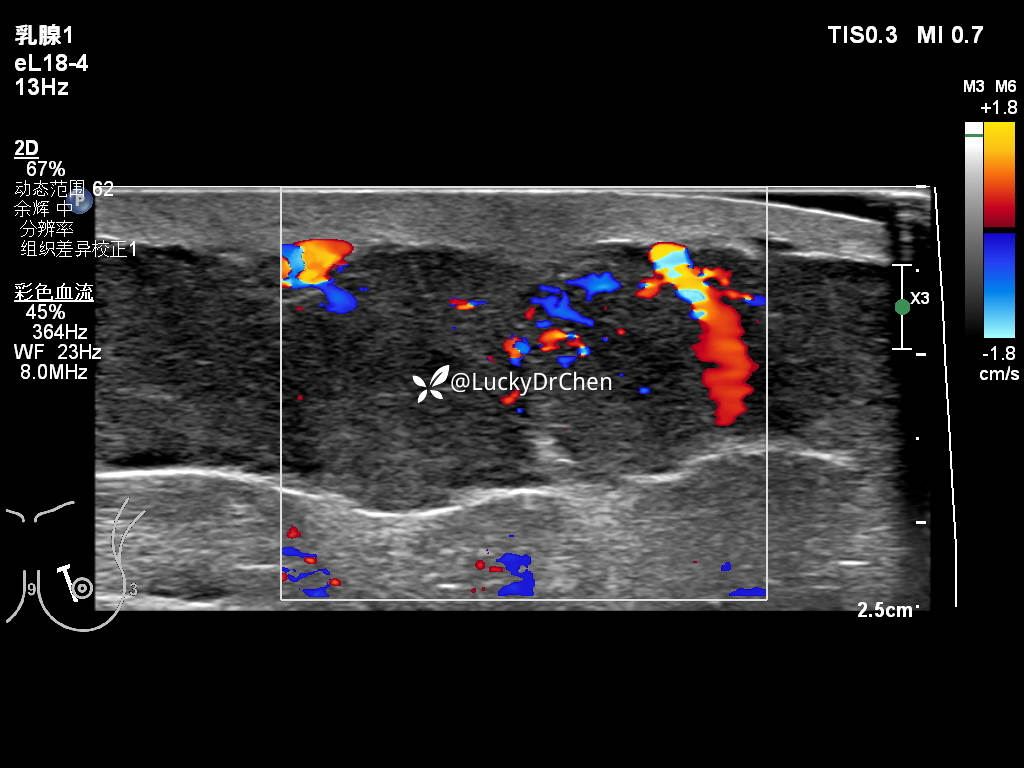

右侧腋下低回声,形态不规则,边界不清晰,周边高回声晕

可见点状血流信号